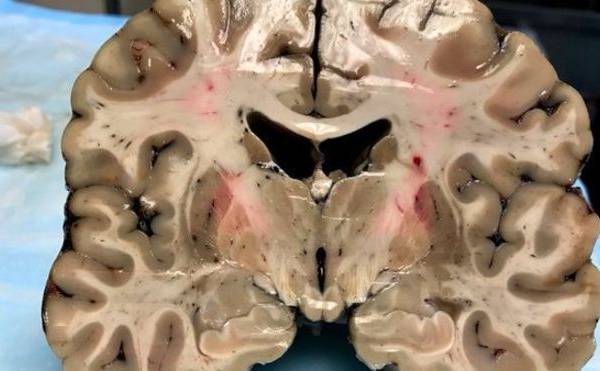

A pesar de su apariencia saludable exterior, el cerebro estaba dañado por encefalopatía traumática crónica.(Foto: B. University)

Colocado sobre una mesa de laboratorio, horas después de su muerte, el cerebro de Aaron Hernández ofrecía una apariencia saludable.

Pero lo que en principio parecía un cerebro sano, escondía debajo de su superficie un secreto que sorprendió a los científicos que llevaron a cabo la autopsia del jugador.

El órgano mostró un estado de encefalopatía traumática crónica (CTE, por sus siglas en inglés) similar al de alguien afectado por esa enfermedad cerebral degenerativa de 60 años.

Al cortarlo en pedazos de 1,3 centímetros, los investigadores notaron la existencia de "cuevas" de un tamaño inusual en el centro del órgano, que se expandían a medida que el tejido cerebral disminuía.

Según Caramelli, se trata de algo poco común para una persona de 27 años, edad en la que el cerebro suele ocupar casi todo el cráneo.

El equipo de McKee también observó que el septo pelúcido, una membrana que divide los dos lados del cerebro, estaba perforada, situación que suele ocurrir con los pacientes que padecen CTE.